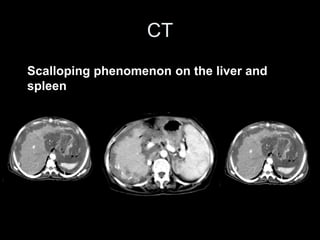

CT

Scalloping phenomenon on the liver and

spleen

• the medical imaging is fundamental in the diagnosis and

the surveillance of this rare pathology. US permits a

better characterization of the ascites whereas the CT

visualizes the calcifications and the scalloping effect.